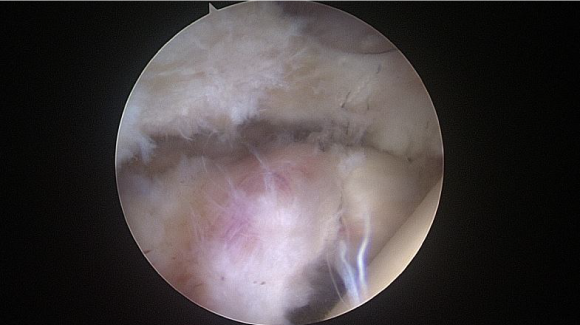

ㆍ비구순 연골파열 및 파열된 비구순을 봉합하는고관절 관절내시경 영상 (2021.10.15)

ㆍ환자 동의를 받은 자료이며, 이미지 사진은 실물과 다를 수 있습니다.